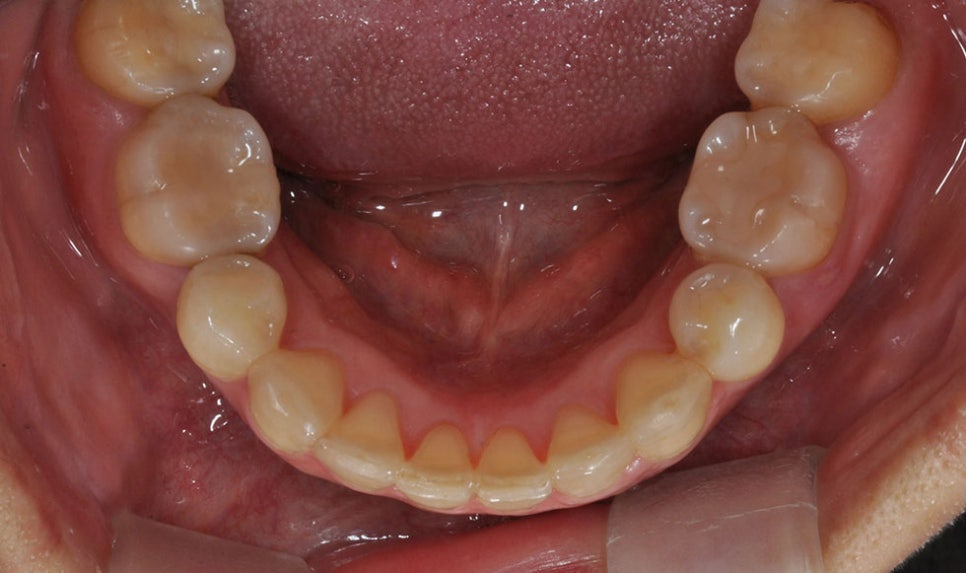

그래피 투명 치아교정의 장점

심미적이고 아프지 않다는

장점을 가지며 교정 효력이 높고

교정 이후의 결과를

예측할 수 있습니다.

또한 간편하고 청결한 관리가 가능합니다.

뉴엔치과만의 맞춤형 3D 투명교정장치

하지만 뉴엔치과 투명교정장치는

3D 프린터로 출력을 하기 때문에

미세한 홈 자체가 없습니다.

따라서 맞춤형 교정이 가능하며

밀착력이 우수하고 이로써

교정력이 우수합니다.